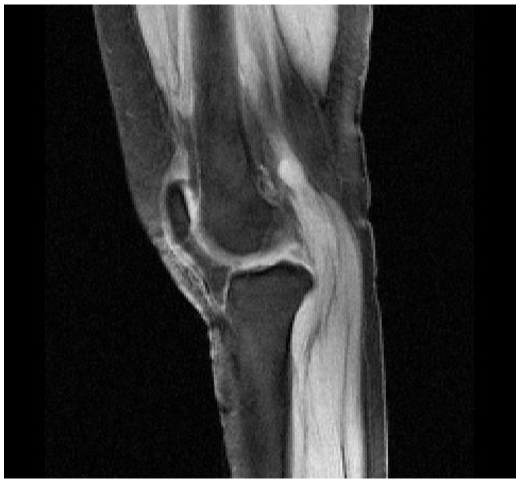

LOW-RES SAGITTAL KNEE